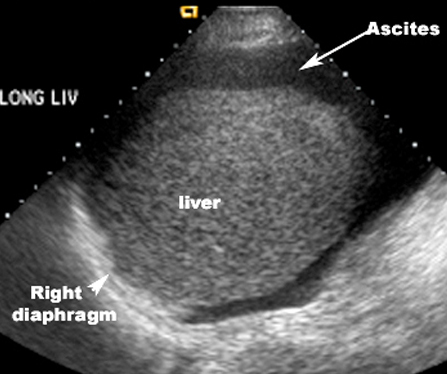

Imaging findings of ascites in ultrasound and CT:

- Ascites is seen as an anechoic space on ultrasound.

- Ascites is seen as low density collection surrounding the bowel in CT.

- Bowel loops float anteriorly.

- Ascites is seen earliest in the pelvis due to its dependent position in the recto vescical or vagino vescical pouch..

- Next it accumulates in the sub hepatic region, in the Morrison's pouch.

US